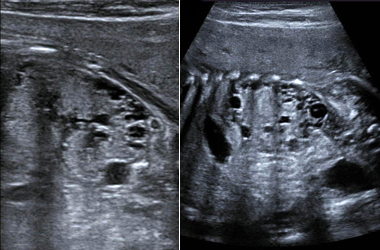

Two images of Multicystic Dysplastic Kidney (MCDK).